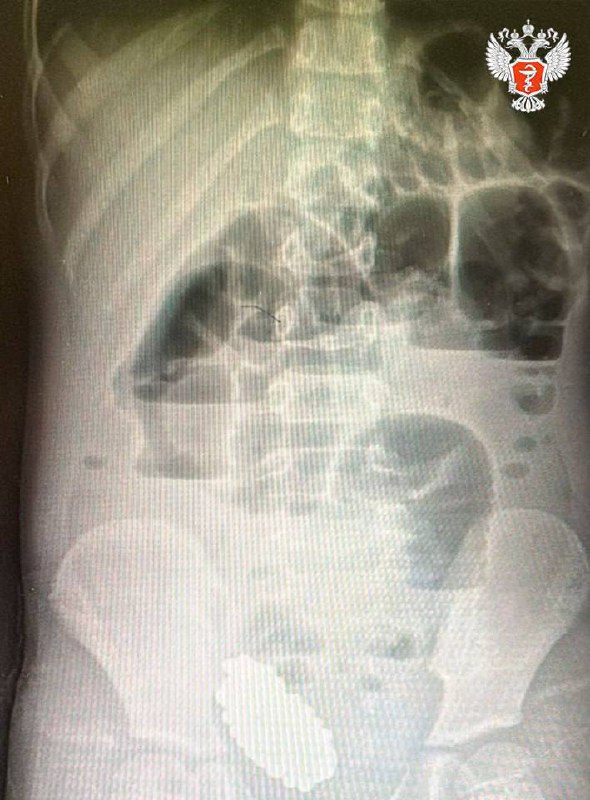

Девочку экстренно доставили в Клиническую больницу скорой помощи №7. При обследовании врачи диагностировали кишечную непроходимость, вызванную инородным телом. Рентгеновское исследование показало скопление слипшихся магнитных шариков, которые сдавливали стенки кишечника.